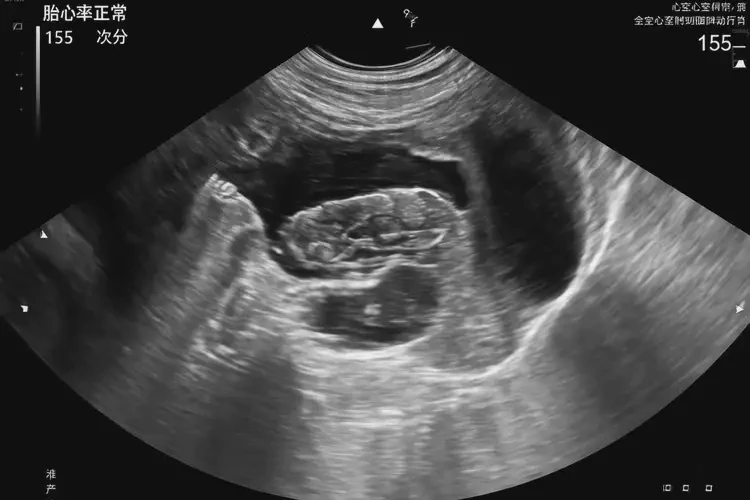

孕13周2天胎心100左右怎么回事

胎心率在孕13周2天時(shí)約為100次/分鐘,屬于正常范圍。胎心率是指胎兒心臟每分鐘跳動(dòng)的次數(shù),是評(píng)估胎兒健康狀況的重要指標(biāo)之一。在孕早期,胎心率通常較快,隨著孕周的增加,胎心率會(huì)逐漸減慢并趨于穩(wěn)定。

孕13周2天胎心100左右怎么回事(圖1)

3. 超聲檢查:通過超聲檢查可以觀察胎兒的心臟結(jié)構(gòu)和功能,并測(cè)量胎心率。

在孕13周2天時(shí),胎心率約為100次/分鐘是正常的。如果胎心率持續(xù)異?;虬橛衅渌贿m癥狀,應(yīng)及時(shí)就醫(yī)進(jìn)行進(jìn)一步檢查和治療。通過定期監(jiān)測(cè)胎心率,可以及時(shí)發(fā)現(xiàn)并處理潛在的胎兒健康問題,確保母嬰安全。